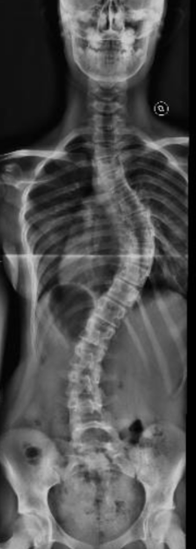

Morena

Inicio del tratamiento:

2018

Edad de la paciente:

10 años

Patología:

Escoliosis Idiopática del Adolescente.

Tratamiento: Uso de un corsé, y ejercicios indicados para prevenir la progresión de la curvatura. Al año: la escoliosis y el valor angular empeoraron significativamente En la primavera del 2020, plena pandemia, se llevó a cabo la corrección quirúrgica. Hoy, Morena ha logrado retomar sus actividades y actualmente juega al hockey. Su evolución refleja cómo, a pesar de las dificultades, se puede avanzar en el tratamiento de la escoliosis.